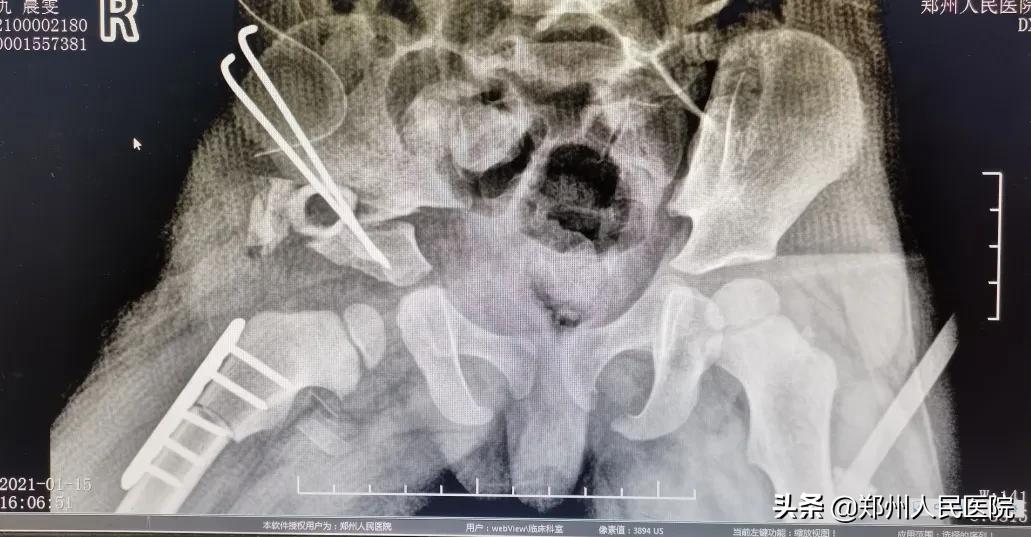

骨科三病区主任医师尹万乐为其查体后发现,文文患肢肌肉萎缩严重、双下肢粗细不一、长短不一、患肢缩短约6cm,骨质发育异常,髋关节磨损加重。

由于文文的髋关节发育不良,且髋关节磨损加重,建议其进行髋关节置换手术。

术前

“患者的情况已经不适合截骨手术,也就是保髋治疗。需要进行髋关节置换,放进一个人工的髋臼杯,再将股骨颈、磨坏的股骨头截掉,换上人工的股骨柄和股骨头,这样就形成了一个新的人工髋关节。通过手术可以解除患者髋关节的疼痛、改善走路一瘸一拐的症状。”尹万乐主任医师告诉小编。